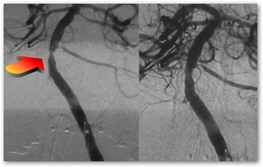

The board's investigation included detailed reviews of five of Midei's cases. In each, Midei wrote in the patient's records that they suffered from an 80 percent blockage of a coronary artery, which needed to be propped open with a stent. But a subsequent review of X-ray images showed less than 50 percent blockage